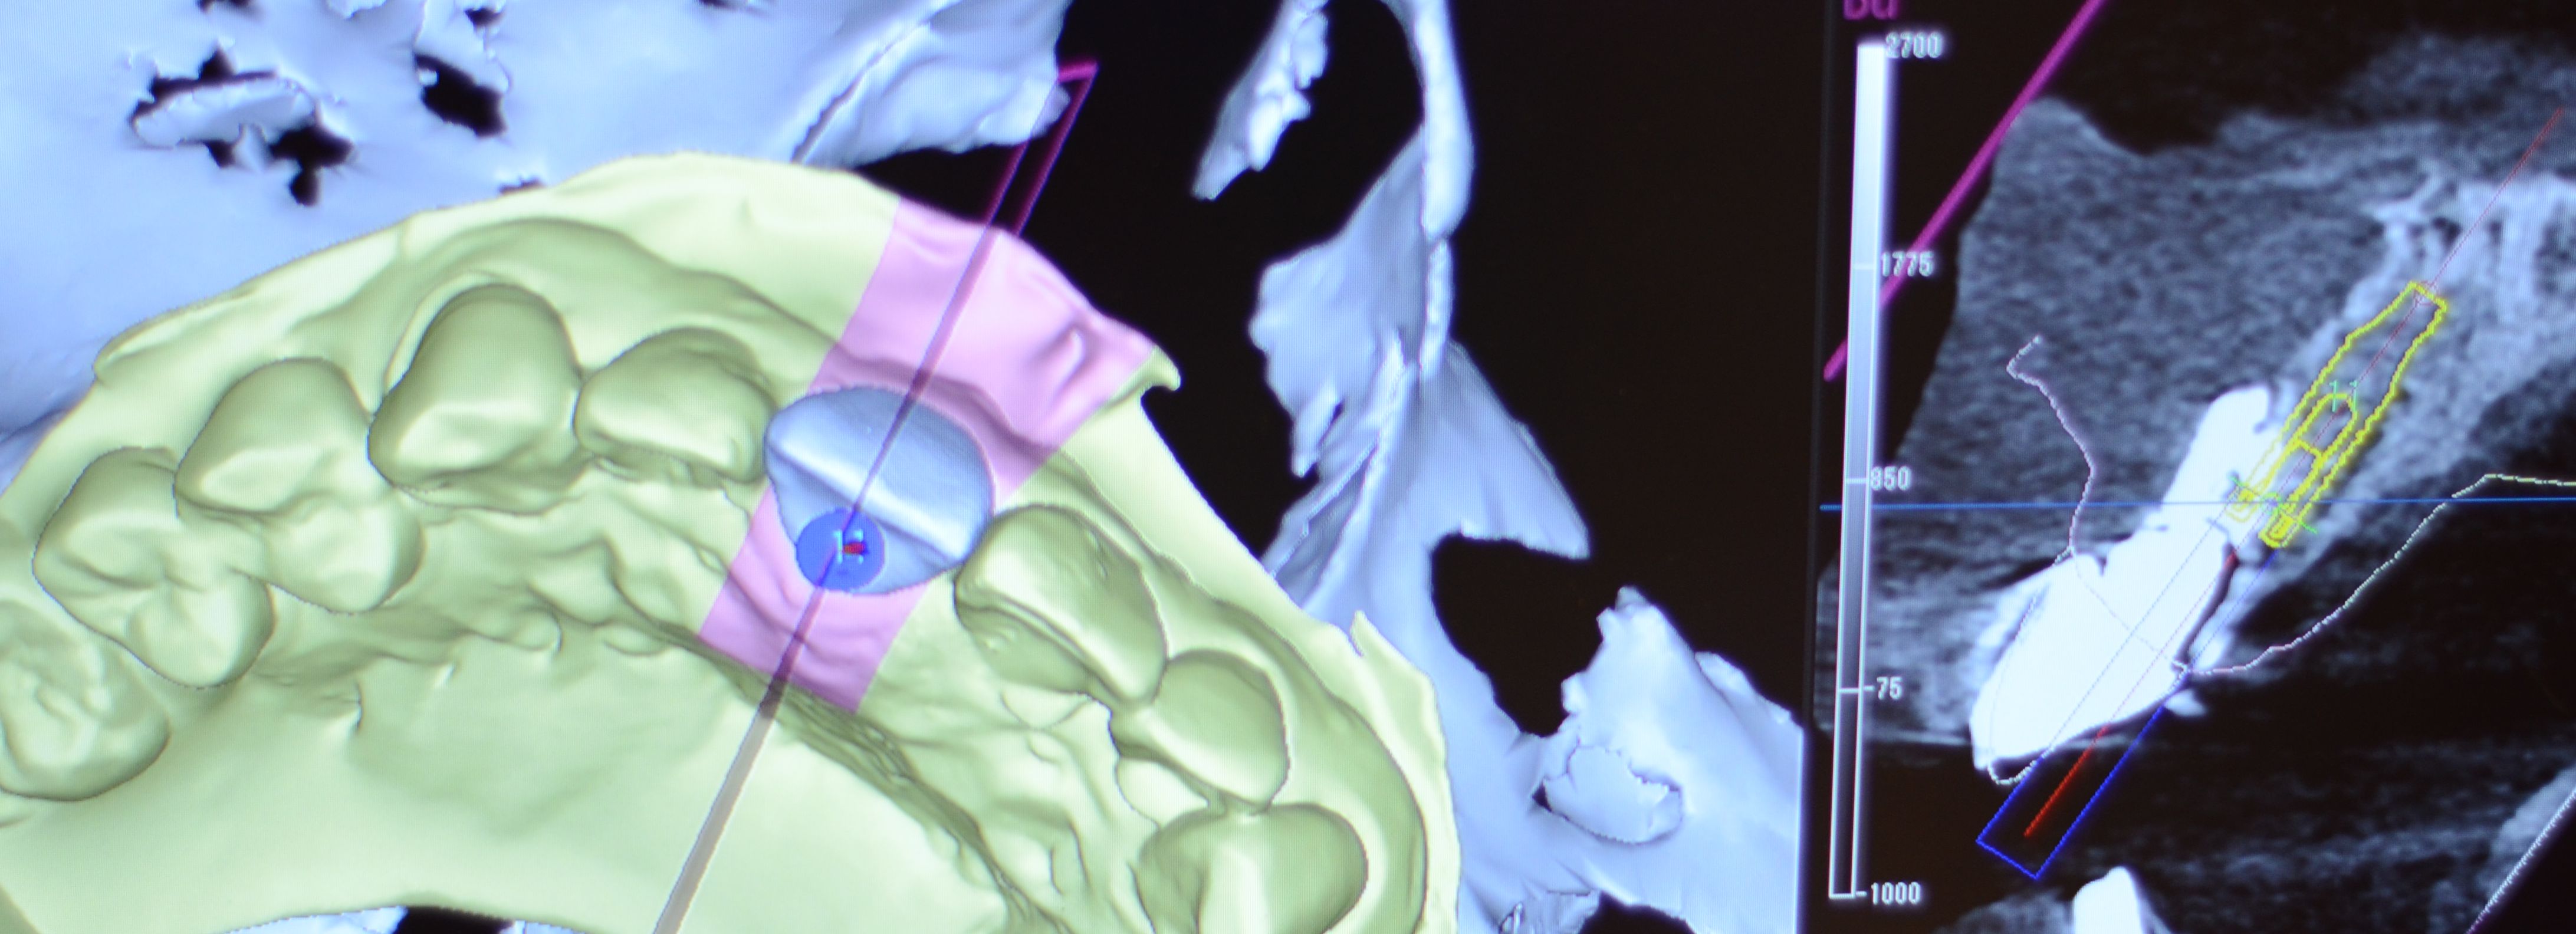

事前にCT撮影と歯型をとり、理想的な位置にインプラントを埋入できるように、サージカルガイドというマウスピースのようなものを作成してから手術を行います。

CT画像による診断

CTデータを実際の口腔内模型と合成し、インプラント埋入のシミュレーションを行います。